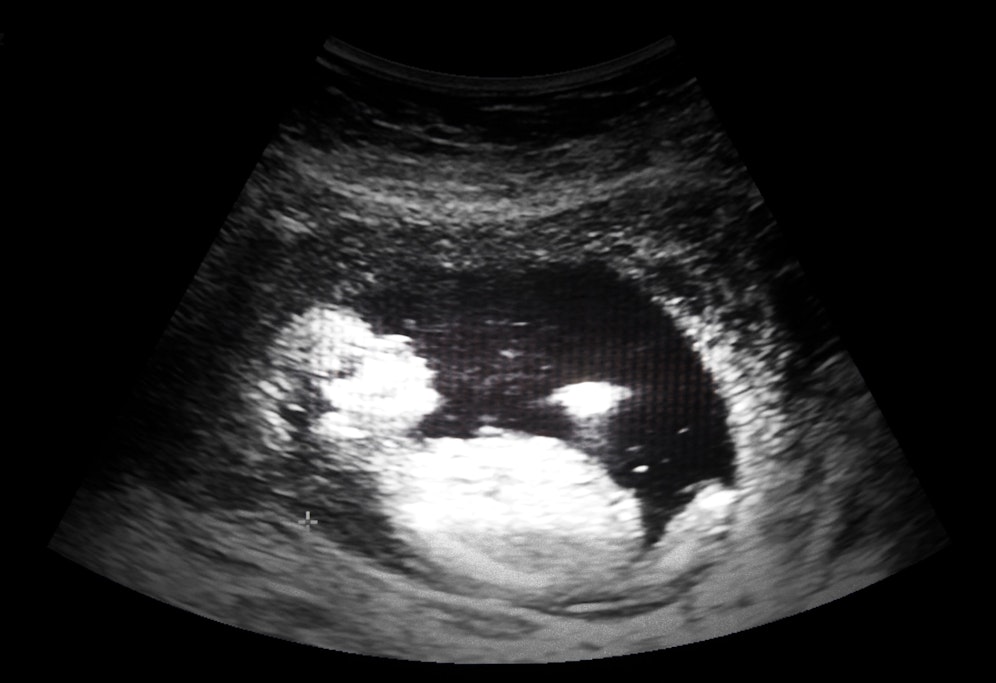

Innerhalb dieser zehn Tage klagt die 31-Jährige immer wieder über Schwellungen, Schmerzen und Atemnot. Zwei Mal durfte sie laut dem Bericht zur Begutachtung in ein Krankenhaus. Als dann jedoch eine Ultraschalluntersuchung anstand, entschieden die Sanitäter, abgestellt vom Department of Health and Social Care, dass sie ihr Zimmer nicht erneut verlassen durfte. Die Begründung: Während der Quarantäne dürfe man nur einmal ins Krankenhaus, Bibi sei schon zweimal gewesen.